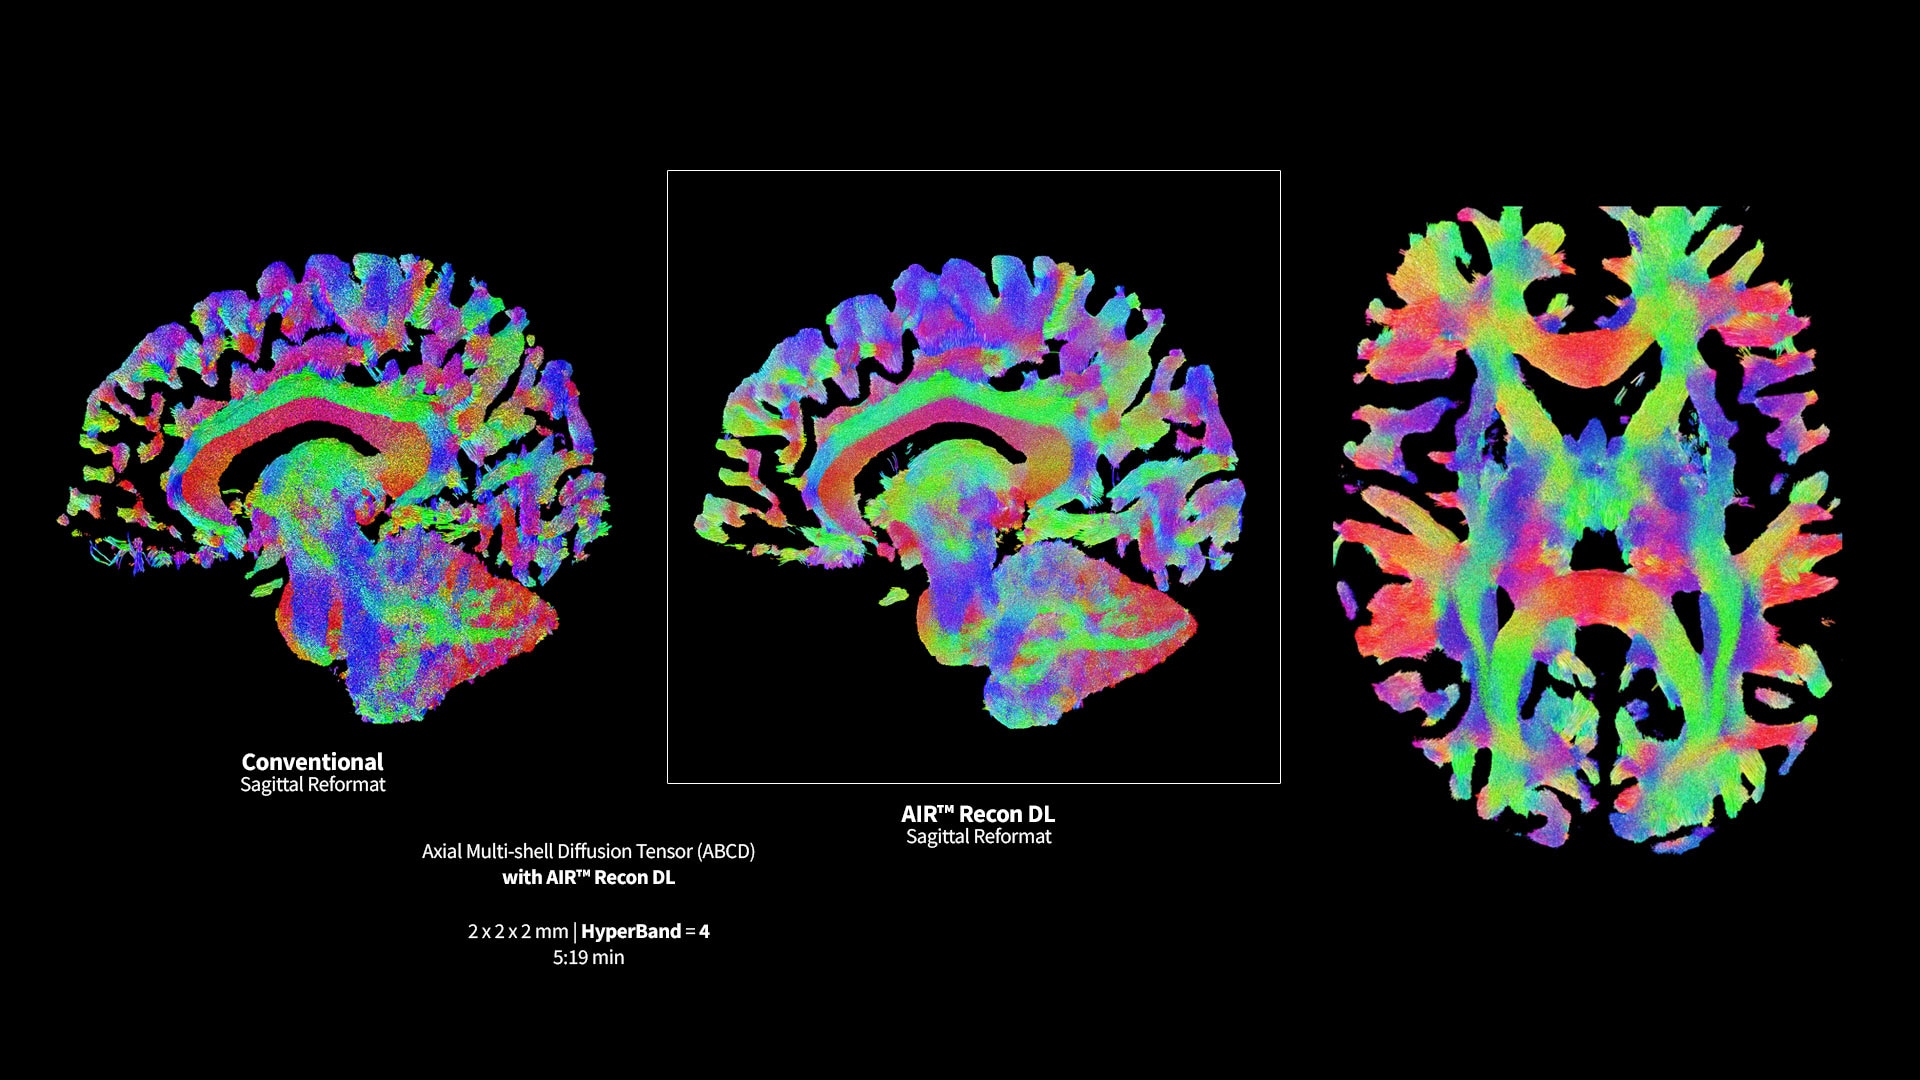

MR image reconstruction with AIR™ Recon DL

AIR™ Recon DL has revolutionized MR imaging with deep-learning based image reconstruction increased image quality, reduced scan time and improved SNR.